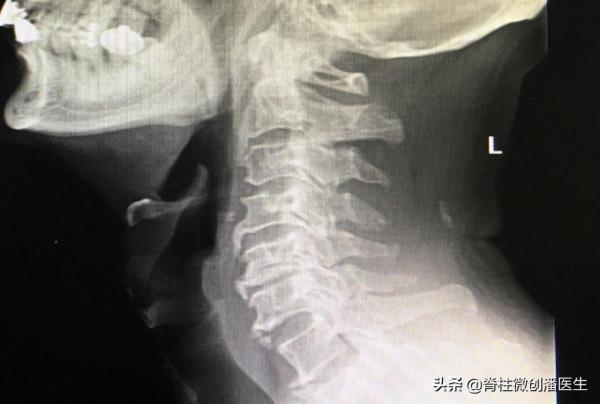

第一是頸椎間盤的退行性變,這是頸椎病的發生和發展中最基本的原因。隨著年齡的增長,頸椎間盤的退變,導致椎間隙的狹窄,關節囊、韌帶鬆弛,頸椎在活動時的穩定性下降,進一步引起椎體、關節、韌帶等等結構的變性、增生和鈣化,這樣形成頸段脊柱不穩定,最後脊髓、神經、血管受到刺激或壓迫,而表現出的一系列臨床症狀和體徵。在這裡我們要注意區分退行性變和退行性疾病,頸椎間盤的退行性變是一個隨年齡增長的衰退過程,這是每個人都會發生的;但退行性變只有在導致出現病理變化了才稱之為退行性疾病。

第三,我們有一部分人由於頸椎先天性的骨性椎管狹窄,導致椎管的生理性矢狀徑小於正常,在這個基礎上,即使頸椎退變發生比較輕,也會出現相應的脊髓、神經根的壓迫症狀而發生疾病。